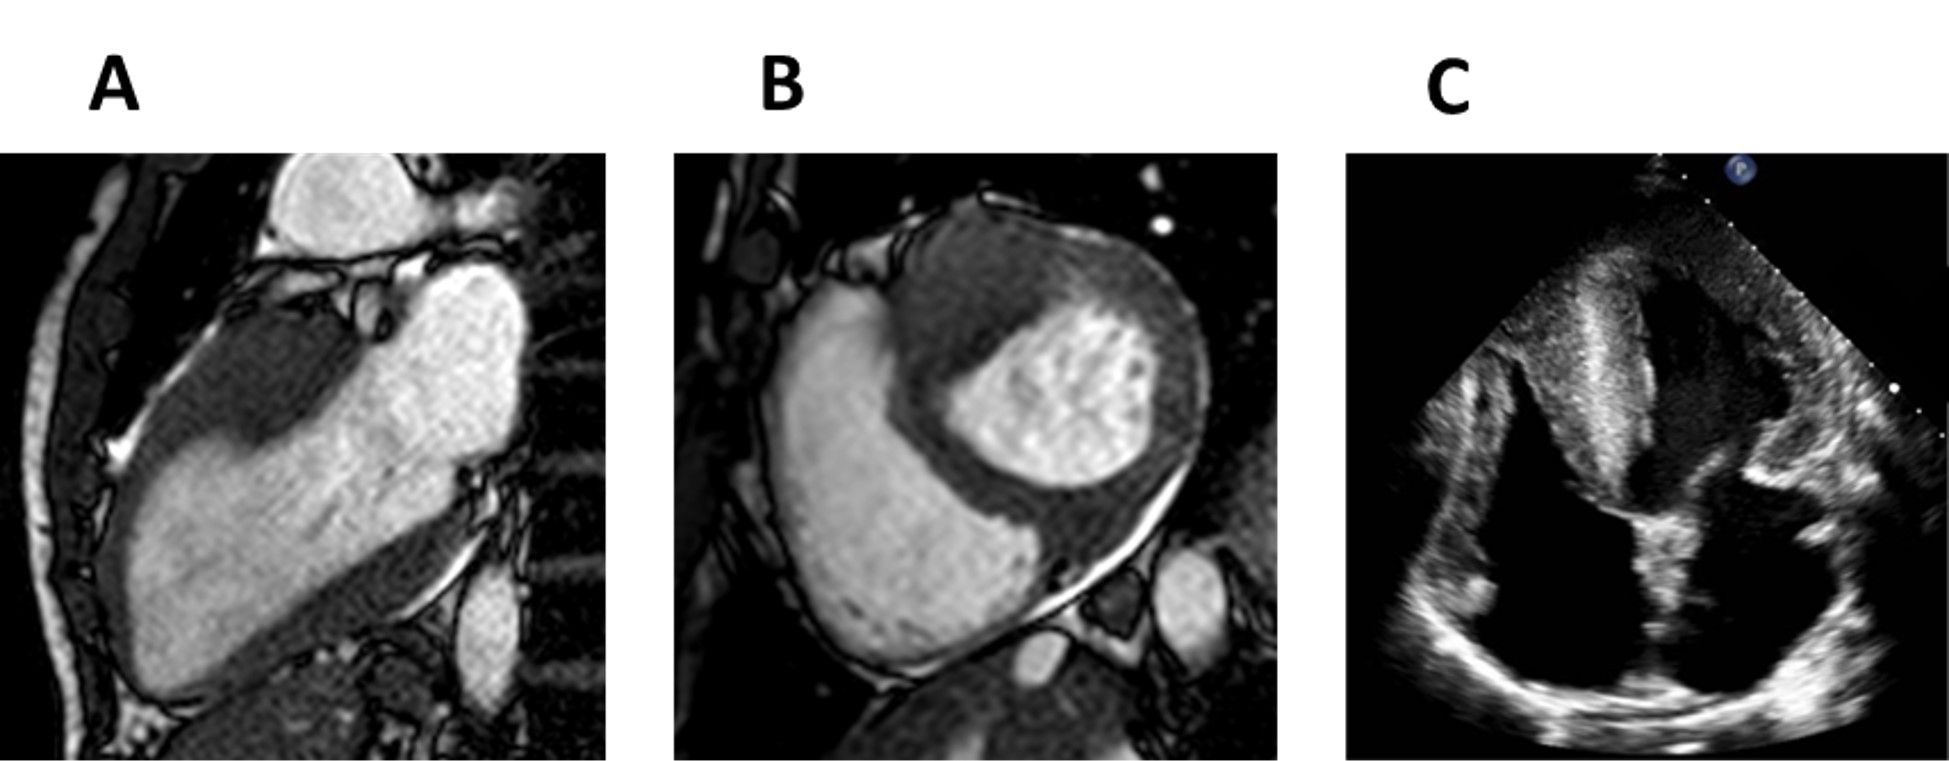

Piecing together all of the previous findings, Nordin et al. [86] was able to construct a three-phase model of cardiac FD progression that subsequently expanded to include a fourth stage based on the findings of Augusto et al. [87]. The proposed phases are as follows: the microvascular, accumulation, inflammation and/or hypertrophy and the fibrosis and/or impairment phase; they are summarized in Table 2 and Figs. 6,7.

Fig. 7.Late stage Fabry disease. (A) Four-chamber cardiac magnetic resonance (CMR) image of a patient with late stage Fabry disease showing severe concentric left ventricular hypertrophy. (B) Short-axis late gadolinium enhancement (LGE) CMR image demonstrating extensive LGE in the basal inferolateral wall (arrow).